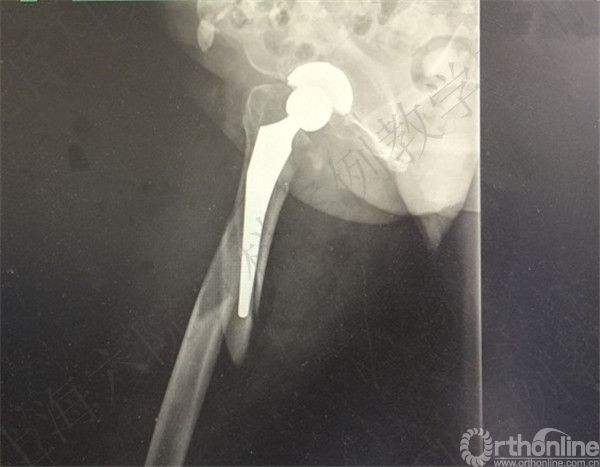

患者2周后自行下地摔倒至右髋假体周围骨折,假体松动,择期行长柄假体置换术+假体周围骨折切开复位内固定术。

术后X线摄片示:假体在位,骨折对位对线可。